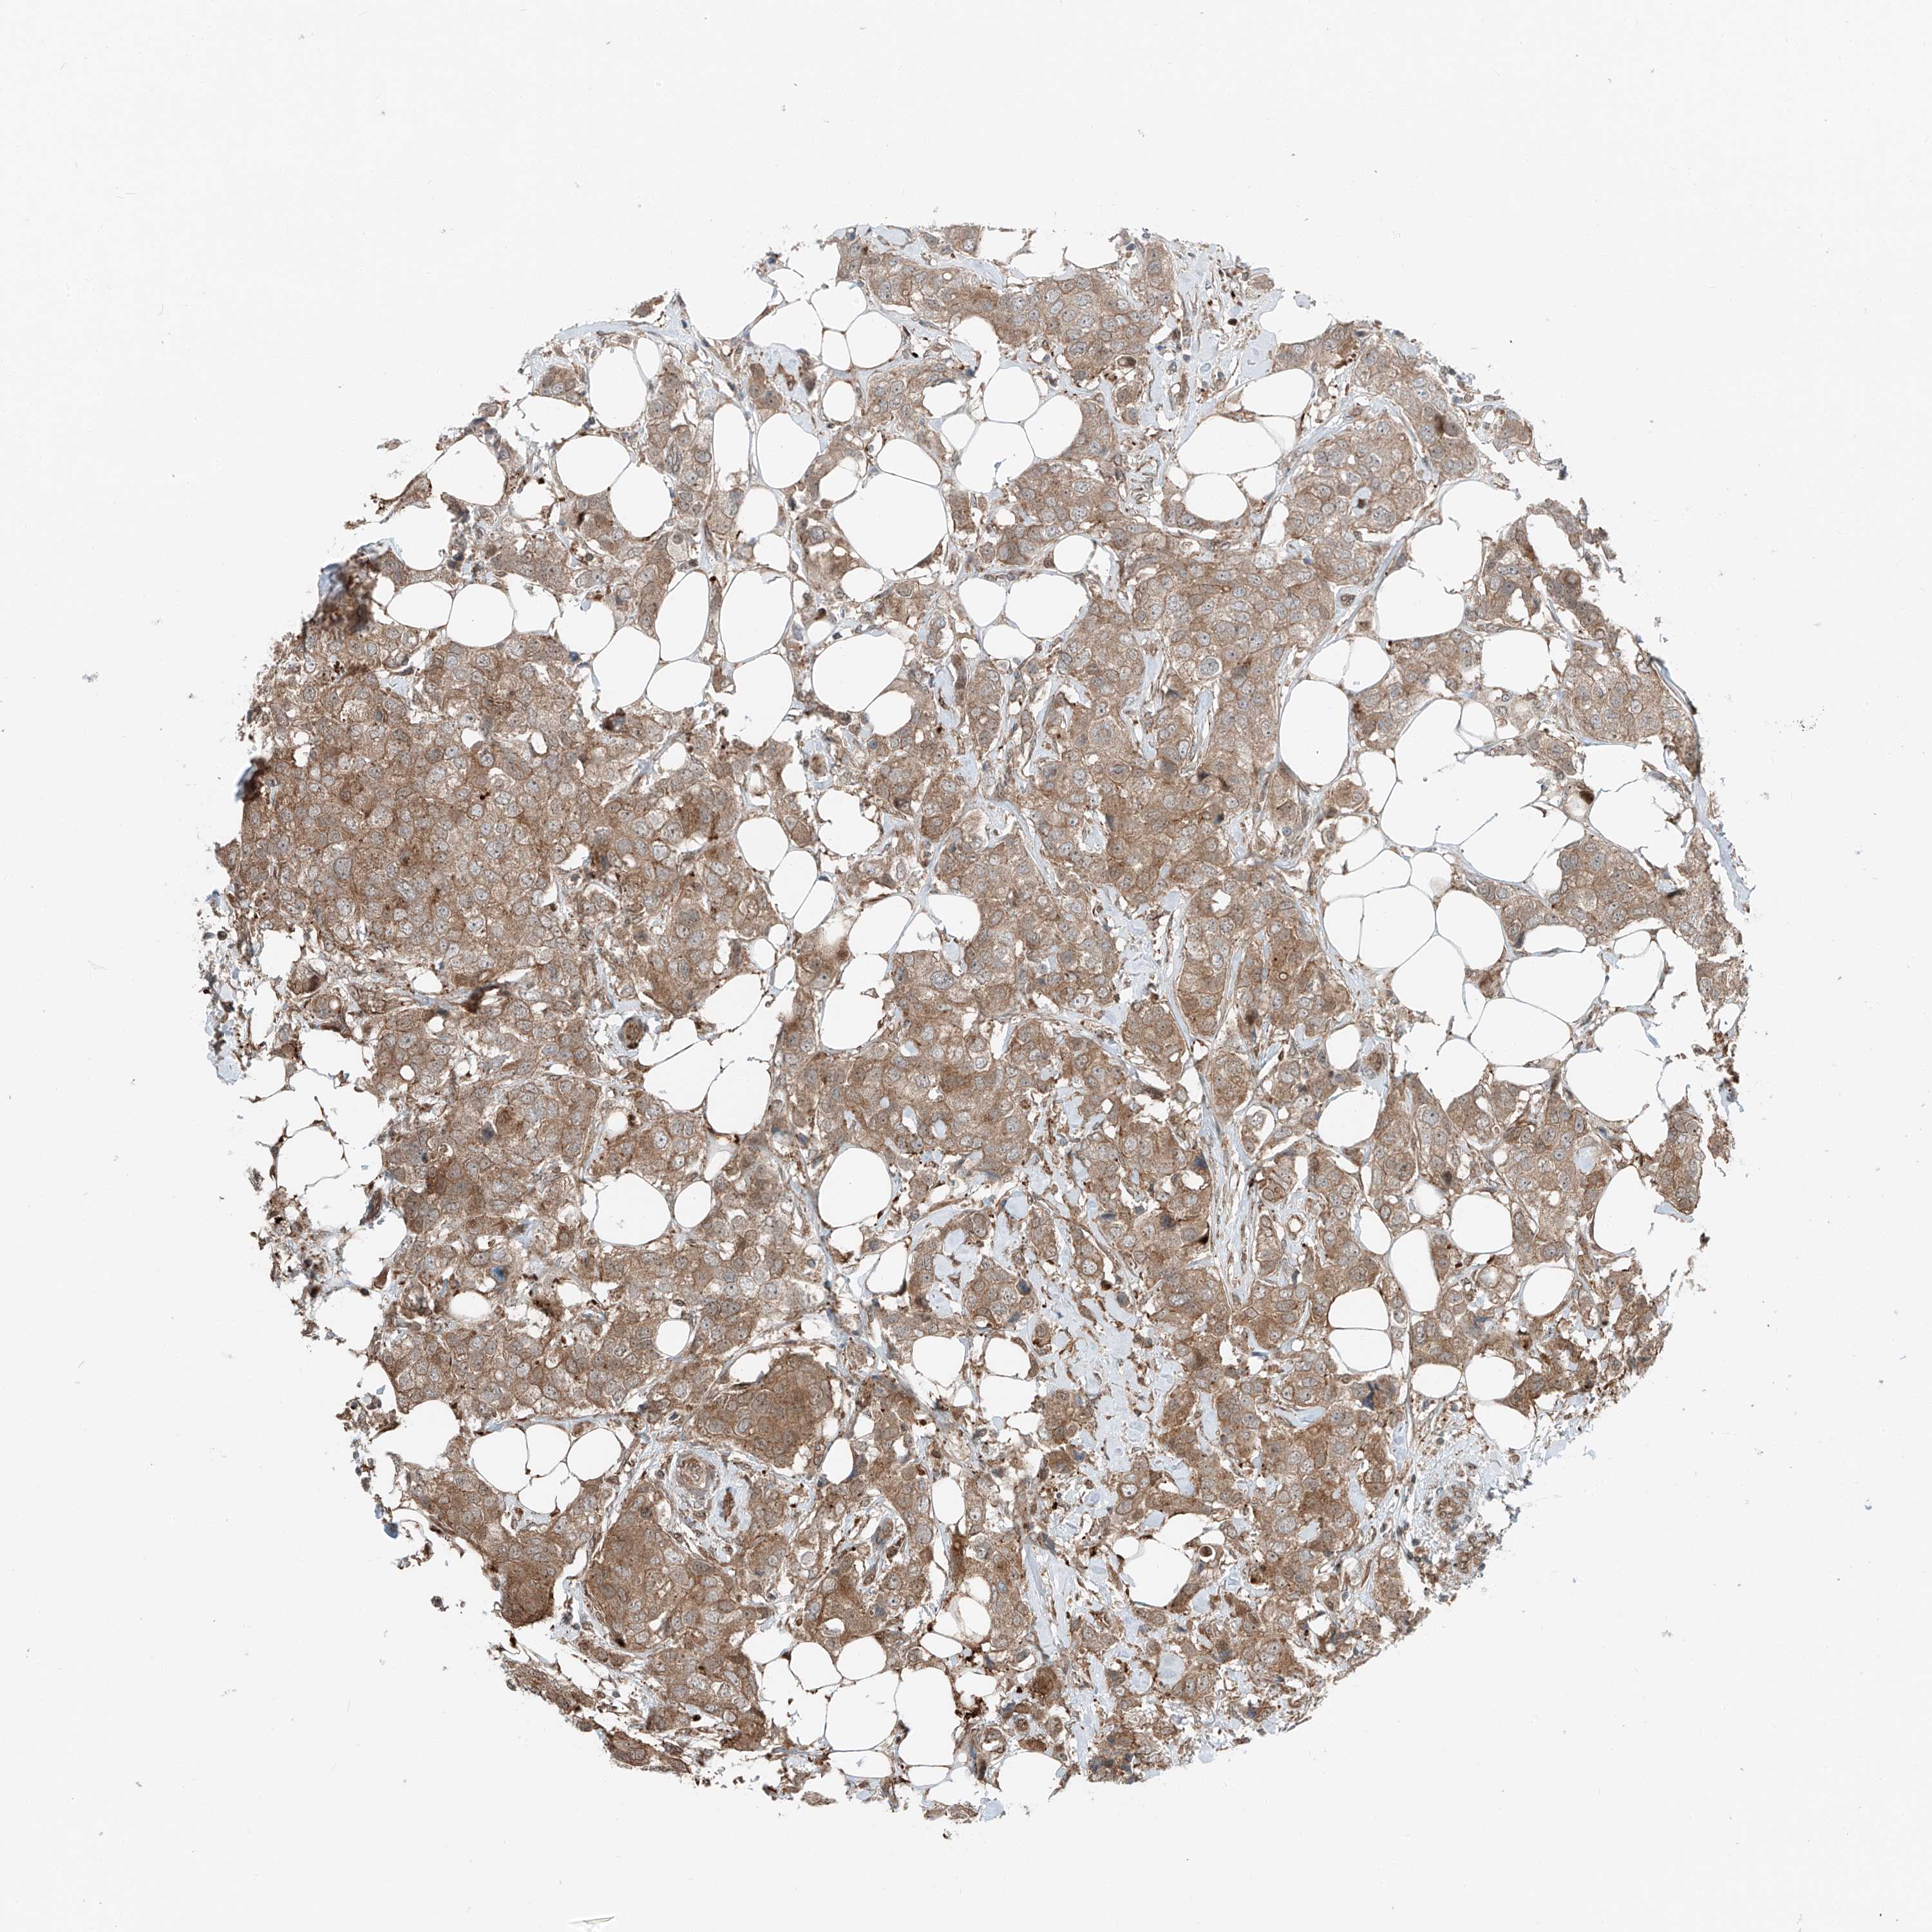

CANCER BREAST CANCER Show tissue menu

BRCA TCGA BRCA VALIDATION PROTEIN EXPRESSION